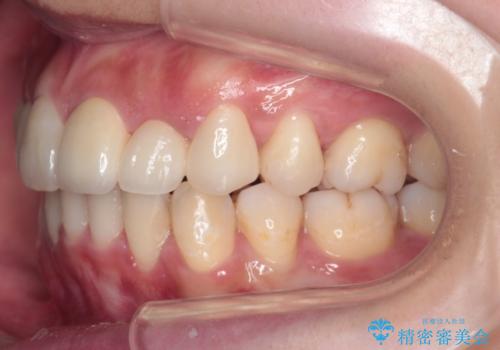

- 歯並びを気にして来院。

乳歯が残存しており、また左上の犬歯もずれて生えてきていました。

右上の前歯も細長い特殊な形をしていました。(矮小歯といいます)

左上の奥歯はすれ違っていたためそのかみ合わせも整えています。

歯を抜いて治療を行ったため、Eラインが整った形で治療ができました。口が断然閉じやすくなっています。